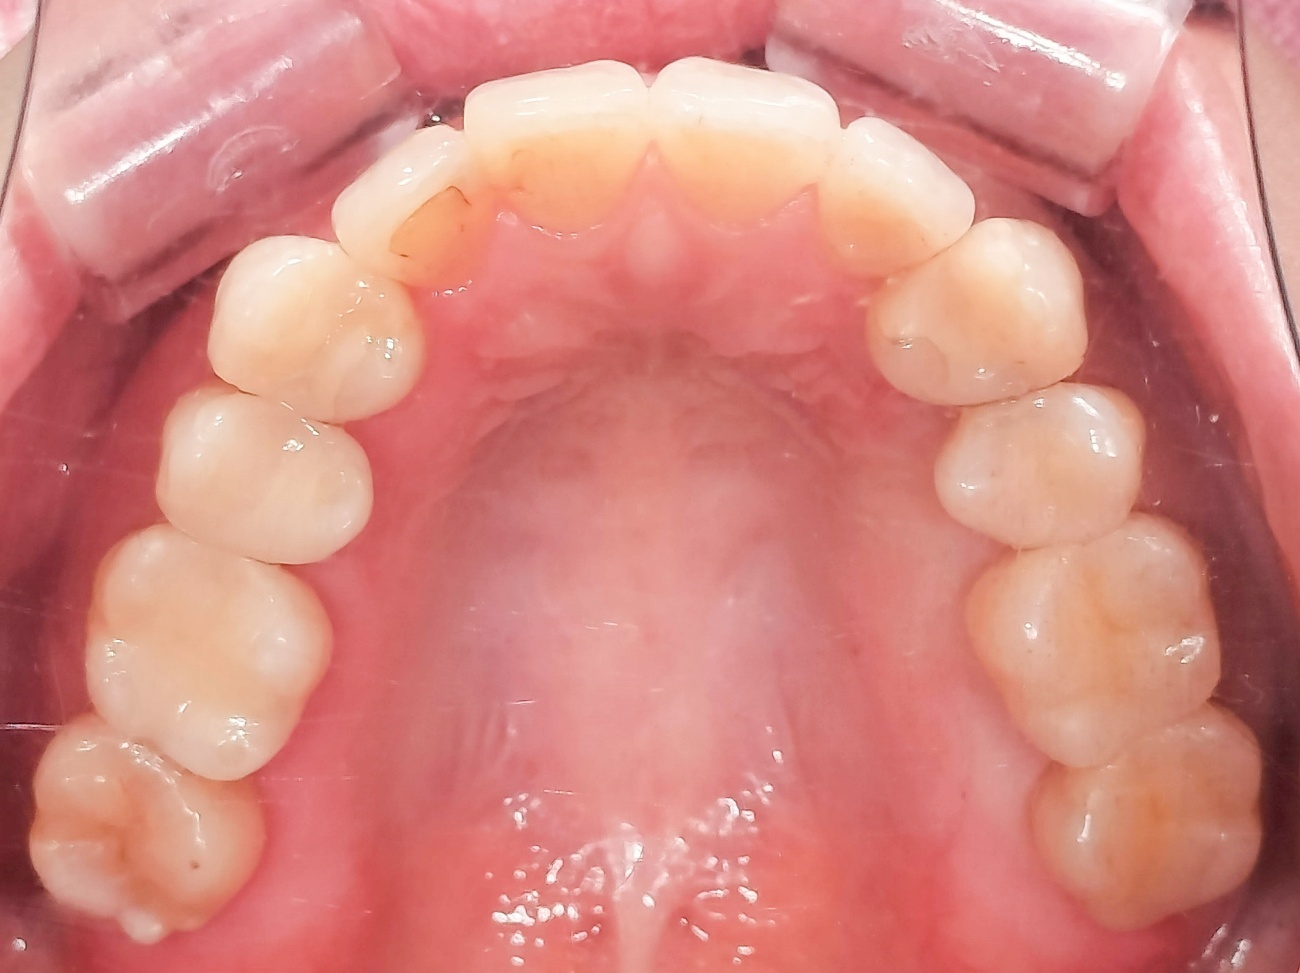

取れてしまった詰め物と金属修復をe-maxインレーで白く自然に修復した症例

Before

After

患者様は、詰め物が外れてしまった部位の治療と、既存の金属修復物を白い材料に変更したいとのご希望で来院されました。

診査の結果、右上5・6に詰め物の脱離部位、左上5に古いメタルインレーが認められました。

機能的な回復とともに、審美性の改善も必要な状態でした。

右上5・6および左上5の計3部位に対し、e-maxインレーによる修復を行いました。

e-maxはガラスセラミック素材で、透明感があり天然歯に近い色調を再現できる特徴があります。

本症例では、噛む力が比較的強くなく、歯ぎしりなどの習癖も認められなかったため、審美性に優れたe-maxインレーを選択しました。

e-maxは透明感があり、周囲の歯質と自然に調和するため、修復部が目立ちにくく、審美的に良好な仕上がりが期待できます。

また、金属修復物をセラミックに置き換えることで、見た目の改善だけでなく、口腔内の統一感の向上にもつながります。

脱離部位は適切に修復され、機能的な回復が得られました。

また、金属修復物が白いセラミックに置き換わることで、自然で違和感の少ない見た目に改善されています。